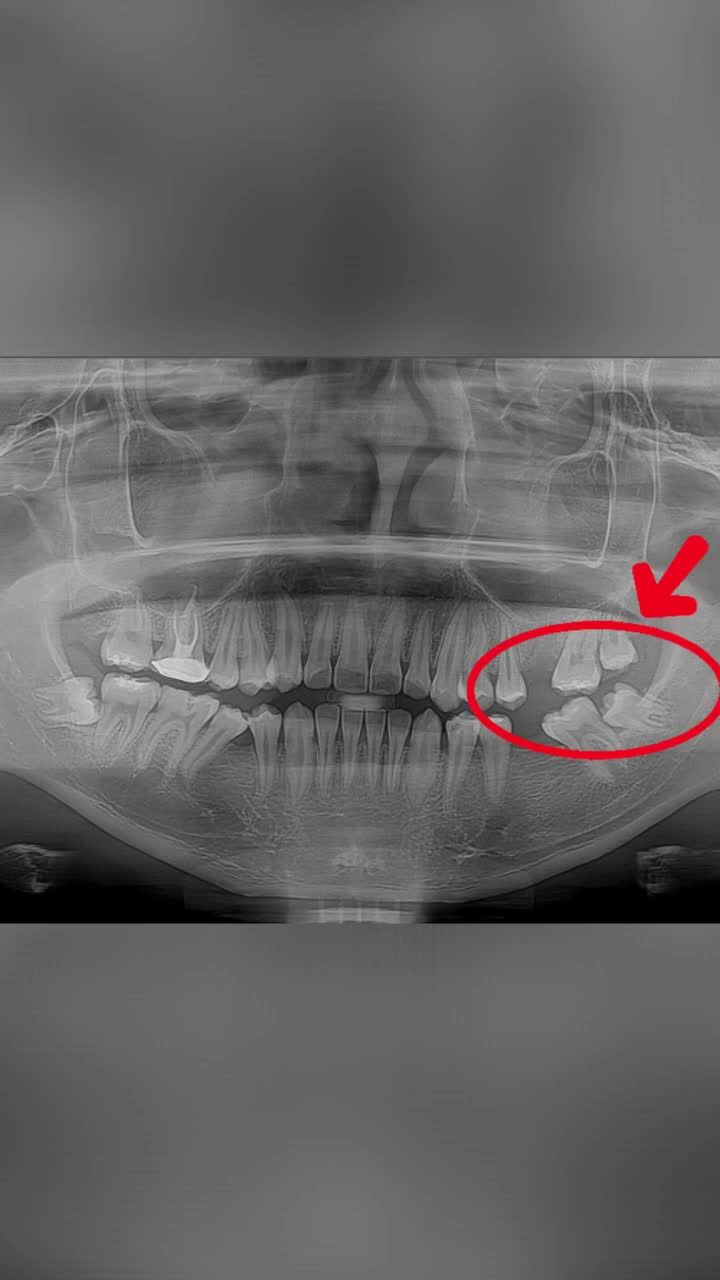

Mất 2 răng 6 niềng kéo răng 7 răng 8